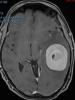

• Lina Carazo Barrios | 30-Mar-2021

Paciente que comienza con cuadro insidioso de inicio gradual y empeoramiento progresivo en dos meses, de alteración en el lenguaje. Inicialmente presentaba leve dificultad para evocar palabras. Consultó en urgencias por empeoramiento rápido con torpeza...

Caso completo | PDF

Neurología: NeurooncologíaEtiología: NeoplasiasDiagnóstico final: Meningiomatosis múltipleNivel de certeza: